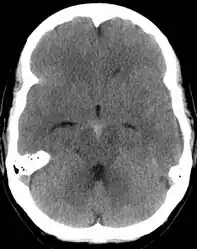

CT scan of the brain showing subarachnoid hemorrhage as a white area in the center and stretching into the sulci to either side (marked by the arrow)

The modality of choice is computed tomography (CT scan), without contrast, of the brain. This has a high sensitivity and will correctly identify 98.7% of cases within six hours of the onset of symptoms.[28][4] A CT scan can rule out the diagnosis in someone with a normal neurological exam if done within six hours.[29] Its efficacy declines thereafter, and a lumbar puncture is also recommended.[1][4] Magnetic resonance imaging (MRI) is more sensitive than CT after several days.[5]